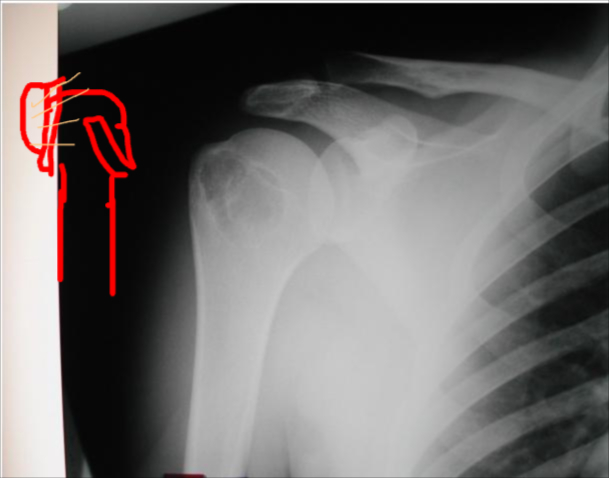

site: Distal shaft of femur size: matrix: Opaque, well defined, ossifying fibroma soft tissue involvement: no peristeal reaction

site: Distal femur size: matrix: soft tissue involvement: